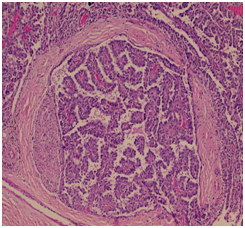

Microscopic examination revealed positive tumor cell for S100 and negative for DOG1, p63, TTF1 and Nose. No extra nodal extension was seen, parotid duct margin was free of tumor, no lymphvascualr invasion, peri-neural invasion was seen (Figure 3). Encapsulated tumor shows cystic changes with area of hemorrhage and extensive papillary formation. Numerous goblet like cells containing mucin were seen, these findings suggested a diagnosis of papillary cystadenocarcinoma of the parotid gland. Without stromal invasion, one lymph nodes showed metastatic tumor. After surgery patient sent for adjuvant radiotherapy.

Figure 3 10X Hematoxylin and Eosin stain shows papillary tumor with perineural invasion and surrounded by fibrous septae.